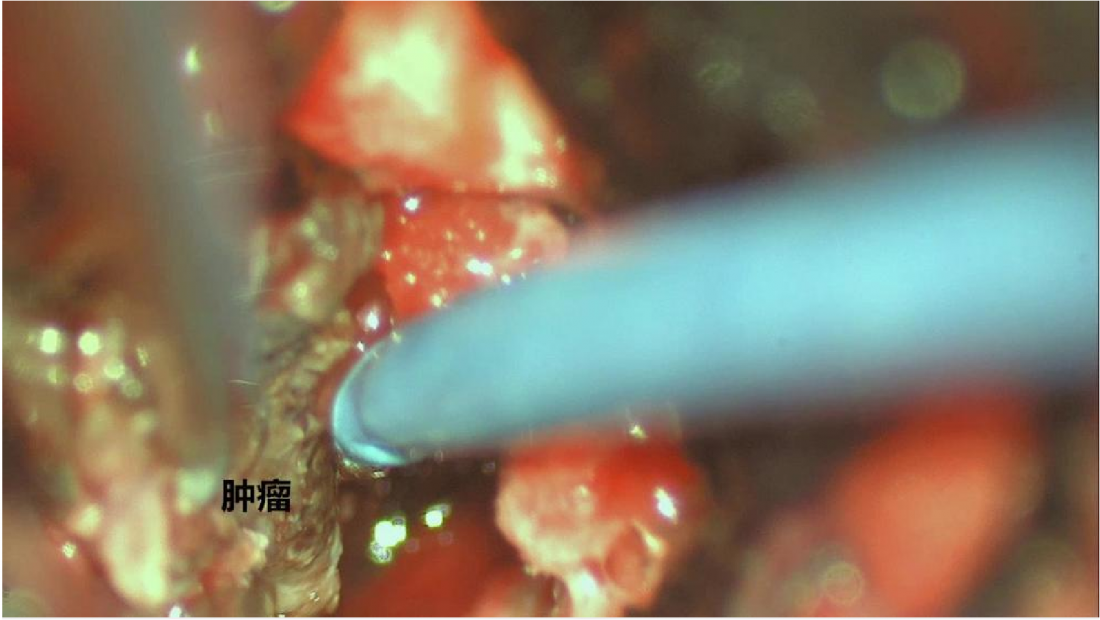

手术入路选择:考虑到患者肿瘤更靠近中线,因此为采取颞下入路及乙状窦后入路。我们采取经枕下正中入路,经第IV脑室切开桥脑,路径最近。因实质性血网手术切除的原则是整体剥除,否则出血汹涌。术中见肿瘤供血丰富,分离肿瘤,完整播出肿瘤。

2、血管网状细胞瘤分为实性及囊性,对于囊性血网的切除原则是切除瘤结节,而非将所有囊壁必须切除。实性血网需要将全部肿瘤部分切除,同时因其血运丰富,手术切除时应整体剥除,而不能分块切除。应该沿着肿瘤的边界仔细分离,因此在脑干内整体剥除肿瘤大大增加了手术的难度。手术时须严格沿肿瘤边界进行,减少对脑干的骚扰。主要最后将肿瘤的供血动脉全部断掉后,才能慢慢取出肿瘤。